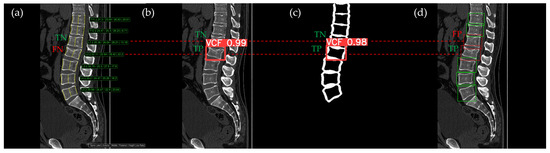

Figure 10, Figure 11, Figure 12, Figure 13 and Figure 14 illustrate typical examples of results for HLR, EEVD, TSVD_SD, and TSVD_DC in patients with acute VCFs. The results of applying different methodologies to the same patient image and identical slice locations were as follows. In the HLR results, each vertebra was marked with yellow solid lines indicating the height measurement lines for the anterior, middle, and posterior regions. The measured height values and HLR percentages were displayed on the right side of the image. If the HLR percentage ranged between 25% and 40%, it was highlighted in orange, while values of 40% or higher were highlighted in red. In the EEVD results, the VCF detection outputs were displayed along with their respective confidence scores based on the input patient images. For the TSVD_SD results, after performing spine segmentation, the model extracted only the spine contour, and the VCF detection results with their corresponding confidence scores were presented. In the TSVD_DC results, bounding boxes were generated for each vertebral body, with normal vertebrae represented in green and vertebrae identified as VCFs displayed in red.

In Figure 10, the acute VCF was present only at the L2 level, characterized by morphological features of an anterior cortical step-off. With the HLR method, the result was an FN, whereas EEVD, TSVD_SD, and TSVD_DC correctly identified it as a TP.

Figure 10. The VCF detection results from four different methods. (a) HLR, (b) EEVD, (c) TSVD_SD, and (d) TSVD_DC. The acute VCF, as confirmed by the radiologist, was located at the L2 level. Both the FN and TP were marked at the same level with a red dotted line.